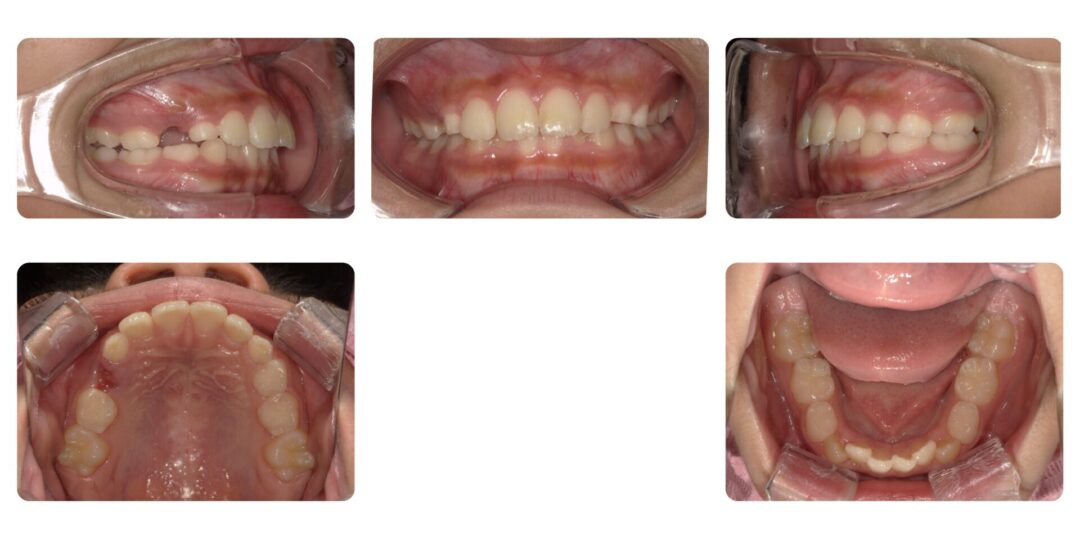

矯正治療前

ご相談内容

下の前歯がガタガタしている

初診時11歳

治療内容

第一期治療 拡大床による歯列矯正→部分的にブラケット装置矯正

治療期間

2年7ヶ月

治療費用

自由診療 基本料金¥330,000 処置料¥3,300(ブラケット期間は¥5,500)